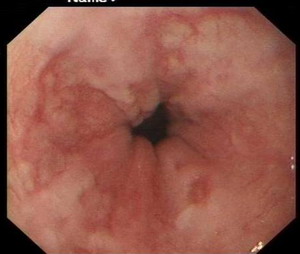

胃镜检查:反流性食管炎A级

萎缩性胃炎

十二指肠黏膜结节不平原因待查

十二指肠降段巨大憩室

胃镜影象